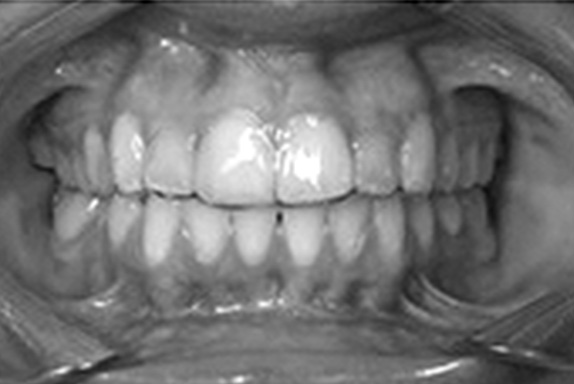

Функцию ретенционного аппарата у пациентов с сочетанной патологией окклюзии зубных рядов выполняли съемный ретенционный аппарат Hawley (рис. 1) и съемный ретейнер собственной конструкции [№ государственной регистрации 2018107373/14(011304) от 27.02.2018 г., авторы Водолацкий В.М., Макатов Р.С.] (рис. 2).

Рис. 2. Съемный ретейнер собственной конструкции (a) в полости рта (b).

Fig. 2. Removable retainer of own design (a) in the oral cavity (b).